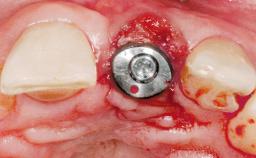

Late Placement of an Implant in a Maxillary Left Central Incisor Site

A 36-year-old female patient was referred for the replacement of the upper left central incisor (tooth 21), which had fractured. Although the tooth had been asymptomatic for many years, the crown began to loosen, at which time she presented to her dentist for an assessment. Teeth 21 and 22 had both been endodontically treated many years previously. She was a healthy individual and a non-smoker.

Type of Implants Two-Piece

Bone Volume Deficient horizontally, requiring prior grafting